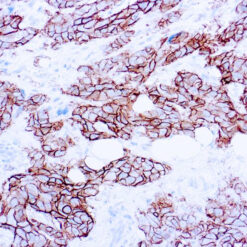

NUT1

NUTM1 is a Protein coding gene. Diseases associated with NUTM1 include NUT Midline Carcinoma and Spindle cell Carcinoma. The molecular weight of this antigen is 120kDa. Among its related pathways are Chromatin regulation/ Acetylation. An important paralog of this gene is NUTM2G. Plays a role in the regulation of proliferation. Regulates TERT expression by modulating SP1 binding to TERT promoter binding sites.

| Cellular Localization | Cytoplasmic, Nuclear |

| Positive Control Tissue | Testis |